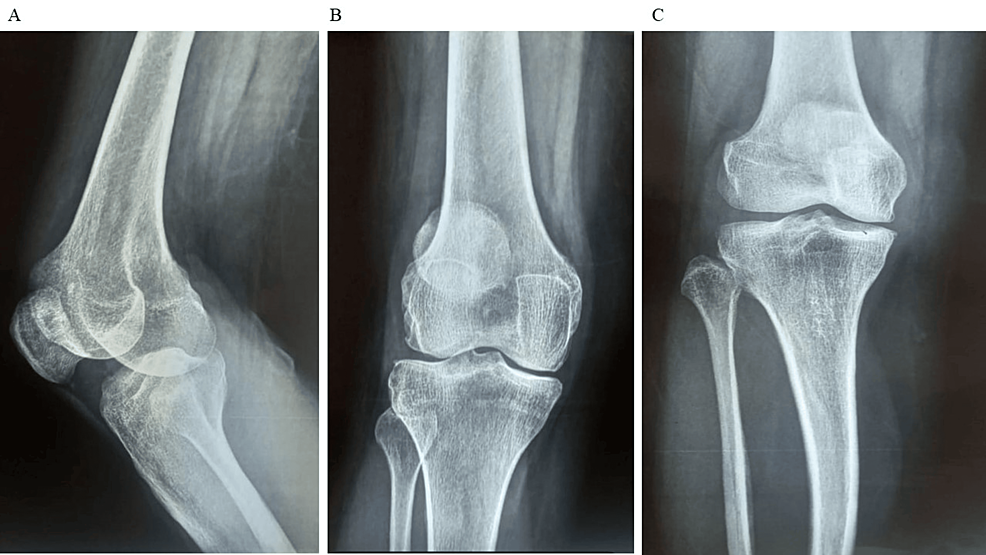

除了骨關(guān)節(jié)炎外,15名參與者還被發(fā)現(xiàn)患有骨缺損,占該隊(duì)列的30%。這些缺損包括各種情況,例如骨折、退行性骨病或先天性畸形,突顯了研究中涉及的骨科問題多種多樣。下圖1顯示了開始干細(xì)胞治療之前的骨骼側(cè)視圖和前后視圖。